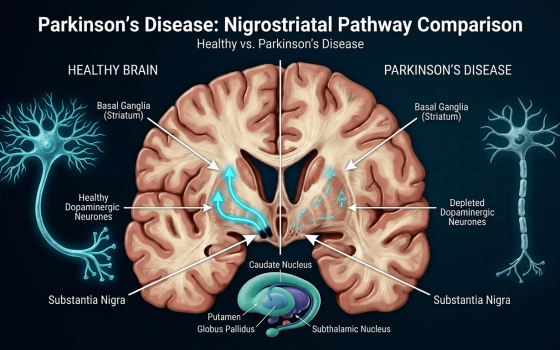

- Parkinson's Disease